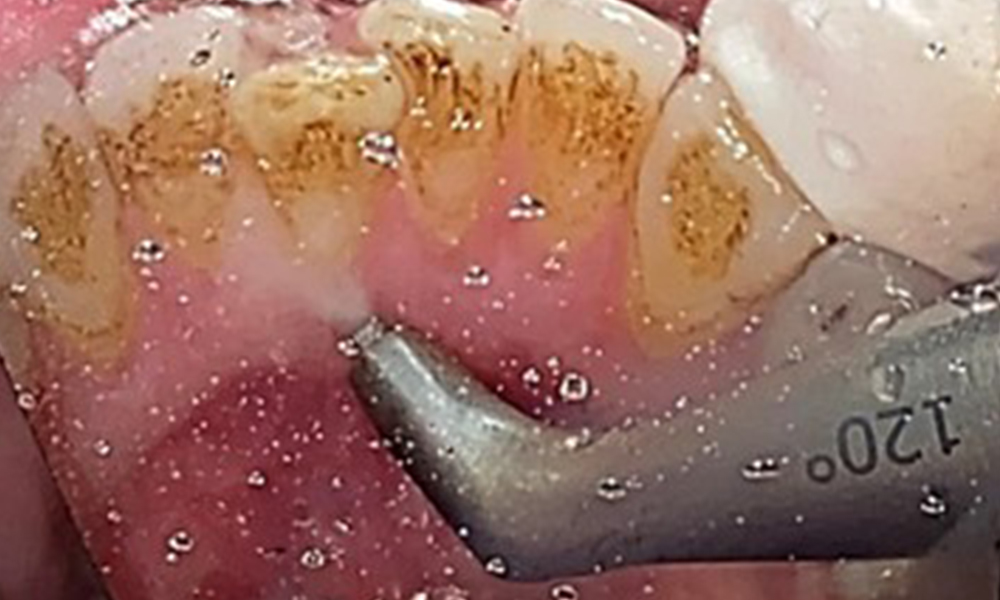

Целта е да се контролира рискът от заболяване чрез отстраняване на супрагингивалния и субгингивалния биофилм. Инструментите трябва да бъдат подбрани въз основа на нуждите на пациента. Първо трябва да се отстранят зъбният камък и всички конкременти с помощта на ултразвукови и/или ръчни инструменти (фиг. 10).